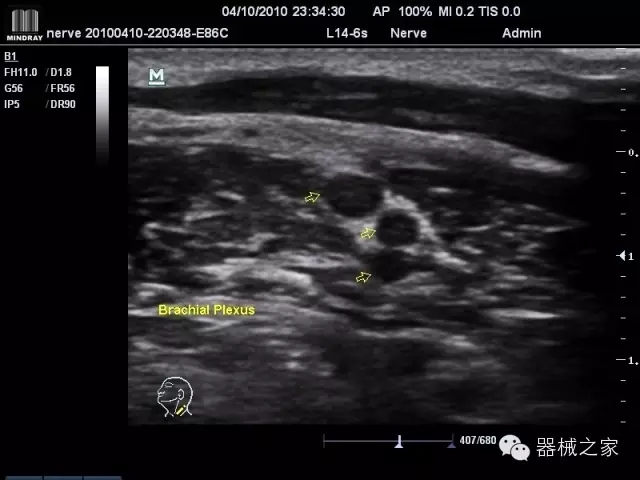

臨床圖片賞析

產(chǎn)品特點(diǎn)

·裝載有采用Multi-Core多核處理的非嵌入式平臺(tái),成像效率大大提高,并且能夠給用戶帶來(lái)高速、多任務(wù)并行信號(hào)處理體驗(yàn);

·優(yōu)秀的圖像效果、強(qiáng)大的功能體驗(yàn)、豐富的探頭選擇、合理的便攜式設(shè)計(jì),全中文顯示及病人管理界面,使得M7在任何場(chǎng)合、任何時(shí)候都能快速響應(yīng)更好的心血管、腹部、婦產(chǎn)、小器官等常規(guī)超聲檢查以及肌骨、神經(jīng)、顱腦、術(shù)中等新興領(lǐng)域的使用需求;